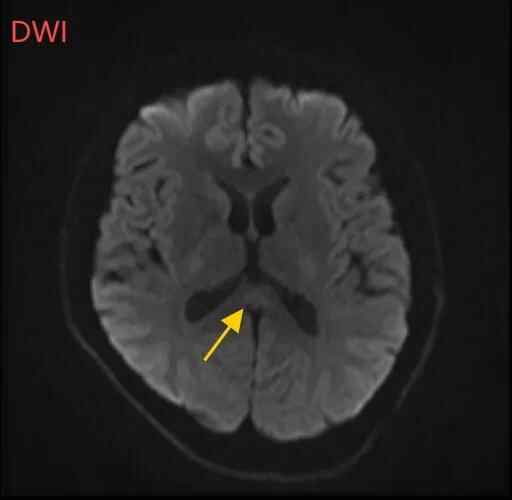

医生摇摇头,经过头部磁共振平扫、弥散、增强影像等检查,医生诊断,小董是得了一种比较少见的病症:可逆性胼胝体压部综合征。

如果把大脑比作一座城市,胼胝体就是连接左右脑的“跨海大桥”,而胼胝体压部正是桥上的“核心枢纽”。当它因酒精、熬夜或感染“肿了”,大脑信号就会“堵车”,引发一系列“故障”。

“压部”病变:胼胝体压部是大脑里的“视觉总监”,眼睛所看到的信息传送到大脑后,由它负责反应整合成图像在脑海中呈现。“压部”发生病变后,就像电视机信号接收不良,屏幕出现雪花一样,眼睛视物就会受到影响。

除了“压部”,胼胝体的其他部位也有病变,所以小董才会出现幻听、手抖等症状。